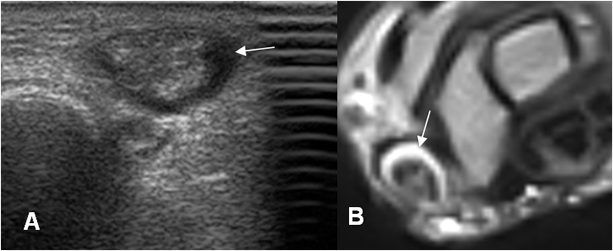

Fig 94 A. Tenosinovitis de Quervain.

A: Ecografía y B: RM axial en T2. Líquido rodeando los tendones del 1º compartimiento extensor, por tenosinovitis.